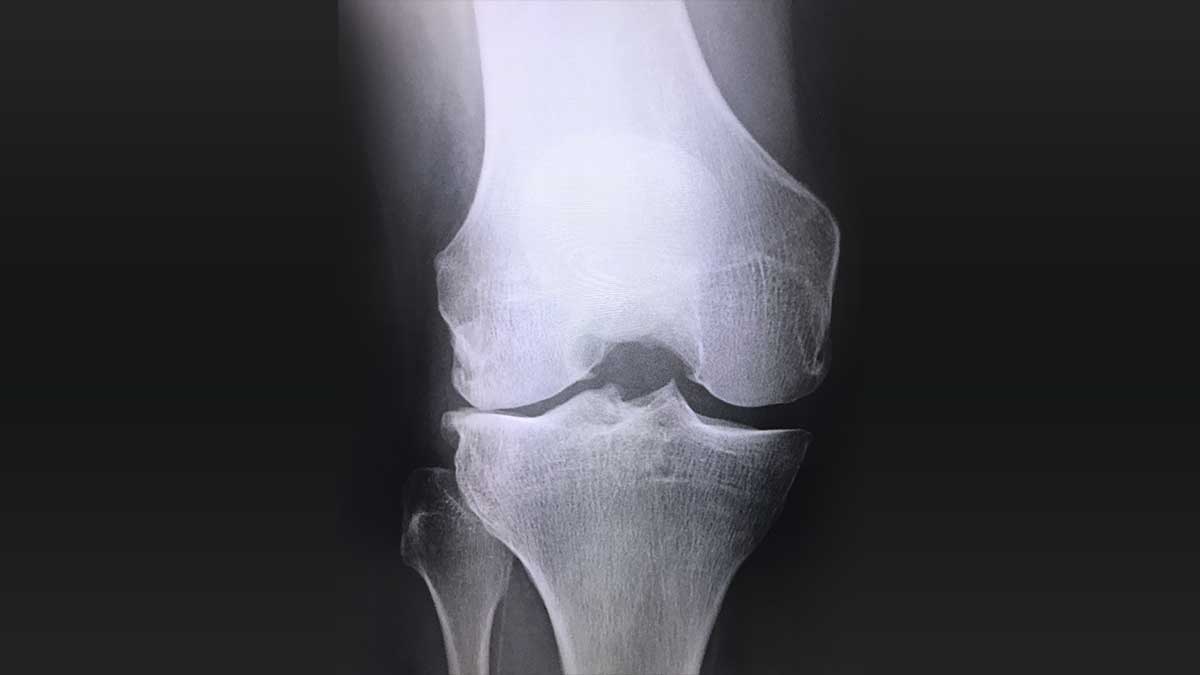

• X線MRIなどの画像処理